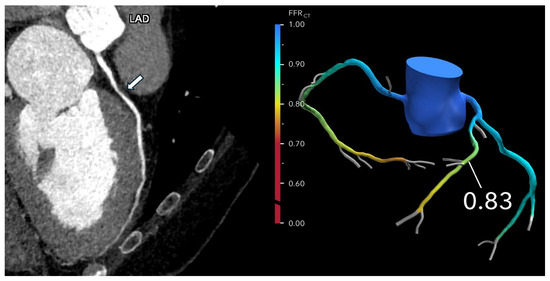

Advances in imaging technologies over the last few decades have revolutionized the role of cardiovascular imaging in the diagnosis and management of patients with cardiovascular disease. Traditional reliance on 2D and 3D imaging has been significantly augmented with the development of advanced technologies, including CT-derived fractional flow reserve (FFRCT), photon-counting CT, patient-specific 3D-printed models, virtual reality and mixed reality tools, and computational modelling, as well as the increasing use of artificial intelligence in cardiovascular disease diagnosis and risk stratification. The aim of this Special Issue is to collect submissions focusing on the use of the latest technologies in cardiovascular imaging. Research areas may include (but are not limited to) the following:

- FFRCT in coronary artery disease;